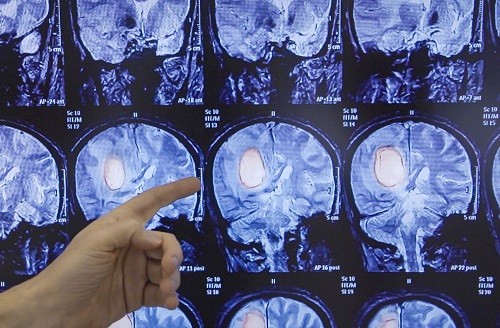

В рамках недели сохранения здоровья головного мозга, приуроченной к Всемирному дню мозга, предлагаем обсудить опухоли головного мозга (ОГМ).

Опухоли головного мозга - это сложные и разнообразные заболевания, которые, как показано в статистике ВОЗ, затрагивают до 6% от всех новообразований в организме человека. Они встречаются у 10-15 человек на 100 000 населения. У взрослых наиболее распространены злокачественные глиальные опухоли (50 - 60%) и доброкачественные менингиомы (18 - 28%).

Для выявления ОГМ необходима консультация врача-невролога с последующим назначением плана обследований, который включает в себя: электроэнцефалографию (для выявления нарушений работы мозга); Эхо-ЭЭГ (для проверки внутричерепного давления); офтальмоскопию (для исследования зрительной функции), КТ и/или МРТ головного мозга. Диагноз ОГМ может быть поставлен только после гистологического или цитологического исследования.